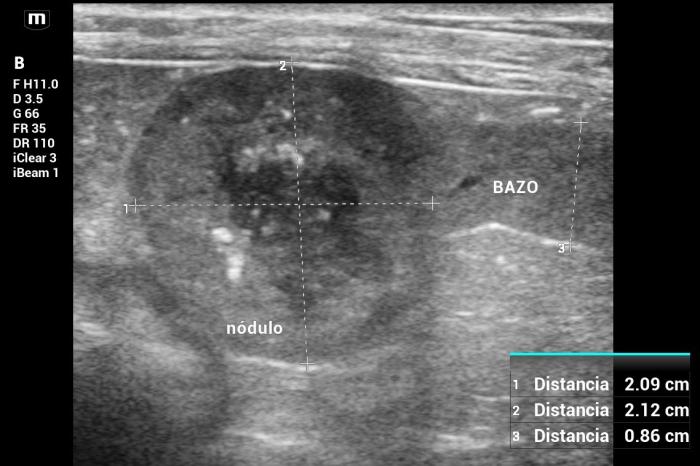

Hallazgos ultrasonográficos (modo B y doppler color): en la cola del bazo, se identificó un nódulo esférico, bien delimitado, de 2.12 × 2.09 cm, con ecogenicidad mixta: un centro predominantemente hipoecoico con pequeñas estructuras puntiformes hiperecoicas periféricas sugerentes de focos de mineralización o densificación tisular (Figura24).

La lesión deformaba la morfología de la cola esplénica y mostraba señal Doppler color positiva, principalmente periférica (Figura25).